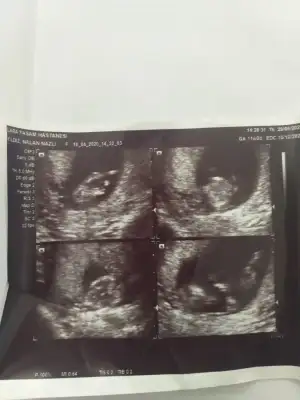

Benim icin de bir tahminde bulunabilir misiniz acaba? :) 4 li resimde sol üsttekine bacakları varmışVarsa 11 12 13 hafta usg ttahmin ederim![]()

Canım hiç net değil usg ler 13 hafta olursa tekrar usg paylaşın şimdilik emin değilim sanki kız ama değilimBenim icin de bir tahminde bulunabilir misiniz acaba? :) 4 li resimde sol üsttekine bacakları varmış

Çok teşekkür ederim 13. Haftada tekrar paylaşırımCanım hiç net değil usg ler 13 hafta olursa tekrar usg paylaşın şimdilik emin değilim sanki kız ama değilim![]()